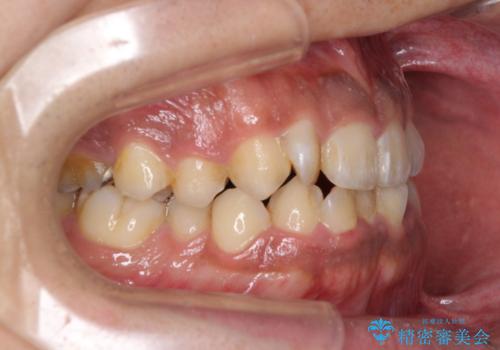

- 前歯のデコボコを気にして来院された患者様です。

前歯が90度近く捻れていたため、しっかりと治すことを考えるとワイヤー矯正の方がおすすめではありましたが、本人の希望によりインビザラインを用いて矯正治療を行うこととしました。

途中2年強の来院がなく、改善されていたデコボコが元に戻ったり、装着時間が不足しており前歯のデコボコは十分に改善することはできませんでしたが、5年間の有効期限内で可能な限り歯列を整えることができました。